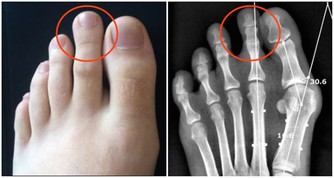

四種表現暗示白血病到來,不可當成小病一直“拖”

後來孩子說自己關節疼,喬女士認為生病了難免會覺得不舒服,自己感冒時也會覺得腰酸背痛的,於是安慰孩子沒關係,很快就會好的。直到她發現孩子身上莫名出現瘀青,牙齦還總是流血,她才意識到有點不正常。拿到報告單後她崩潰大哭,覺得是自己害了孩子,要不是自以為是拖這麼久,說不定孩子早就接受治療了。

醫生提醒:孩子貧血沒有精神、頻繁發燒降不下來、鼻腔牙齦莫名出血、關節疼痛水腫,這些都可能暗示白血病到來,若是經過用藥還沒有緩解,就不要再拖下去了,盡快就醫檢查。